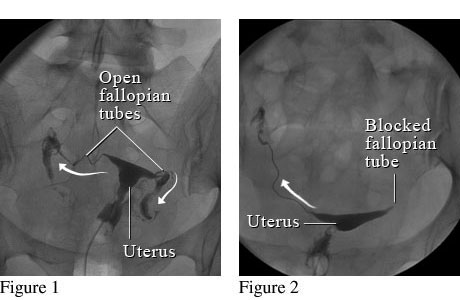

그래서 만일 나팔관이 막혀 있지 않다면 자궁안을 채우고 난 이후 나팔관으로 순차적으로 조영제가 빠져 나가는 것이 확인이 되겠지만, 만일 자궁에 혹이 있는 경우엔 그 부분이 검게 뚫어져 있을 것이고, 나팔관이 막혀 있다면 나팔관 바깥쪽으로 조영제가 빠져 나가질 않을 것입니다.

그림1. 정상 나팔관 모습          그림2. 한쪽 나팔관이 막혀 있는 모습